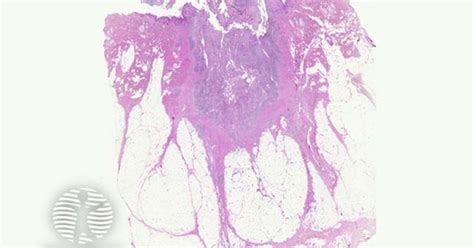

Pilonidal sinus , at its core, is a small hole or tunnel in the skin. Typically, it develops in the crease of the buttocks, near the tailbone. Imagine a tiny pit stop for debris like hair and dead skin cells – that’s essentially what it is. Over time, this collection can cause irritation, inflammation, and even infection. Trust me; you don’t want an infection in that area!